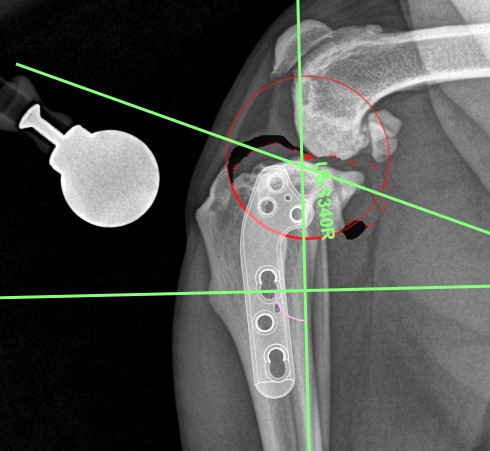

TPLO Pre Op Plan